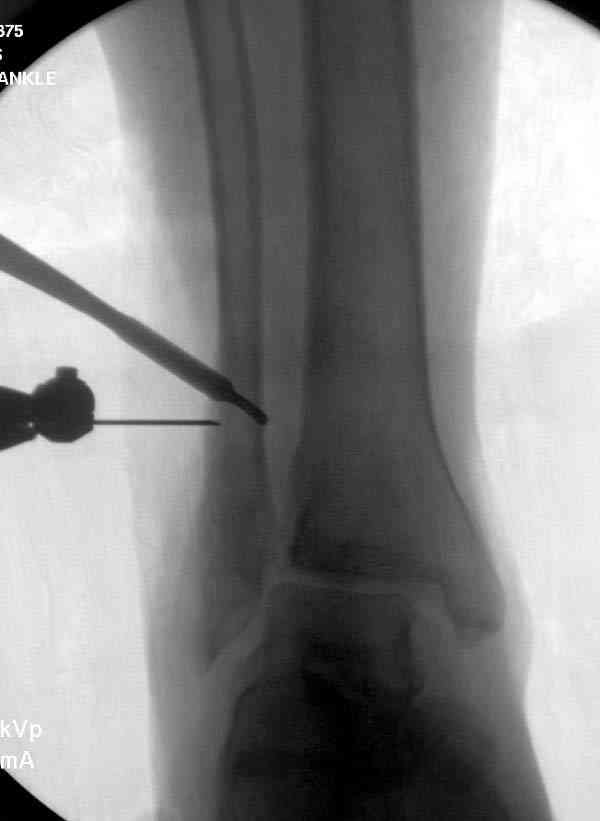

Здесь представлено решение похожей проблемы. Больной в течение года лечился консервативными мерами, и боли в голеностопе были основным показанием к операции.

Проведена обычная стандартная процедура по исправлению неудовлетворительного состояния голеностопного сустава, где кроме удлинения малоберцовой с применением compression tension device за проксимальный конец пластины, проведено замещение трикортикальным графтом из крыла, освобождение синдесмоза и медиальной щели от

фибротических масс с фиксацией.